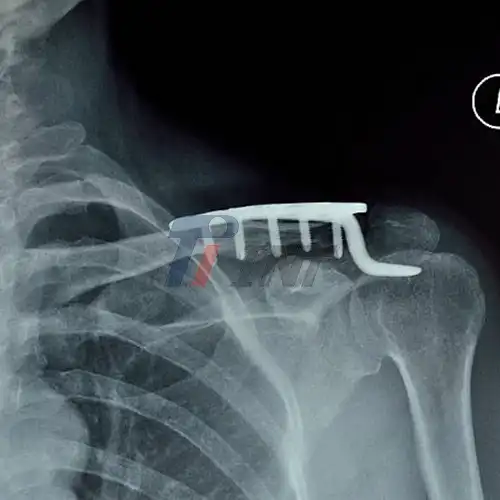

2025-06-24 10:06:14Titanium Plate for Clavicle Fracture: Benefits and Recovery Tips

2025-07-30 09:22:17Clavicle Fracture Treatment with Titanium Plates: Healing Explained

2025-08-22 09:45:57Advanced Titanium Plate Solutions for Collar Bone Treatment in Trauma Care